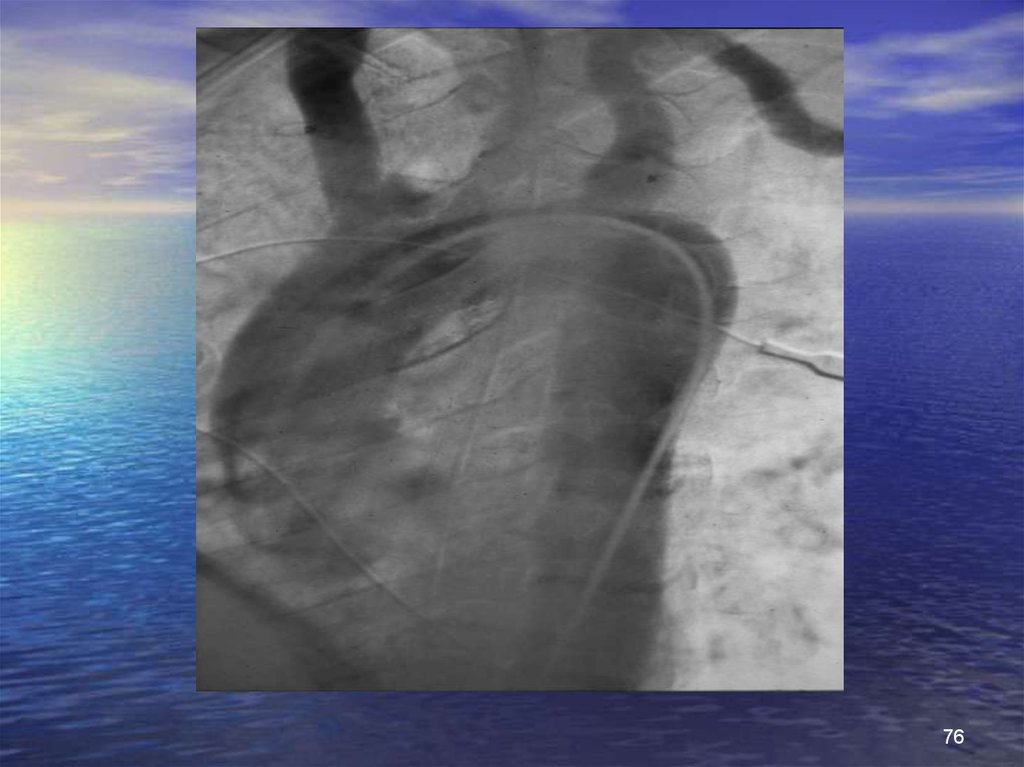

76.

76